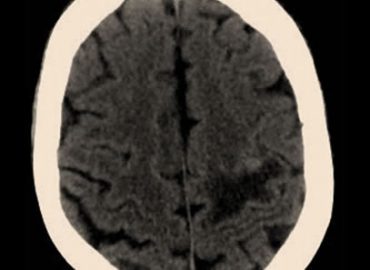

Paciente femenina de 35 años que consulta por mareos y diplopía. APP: hepatitis autoinmune (hace 11 años).